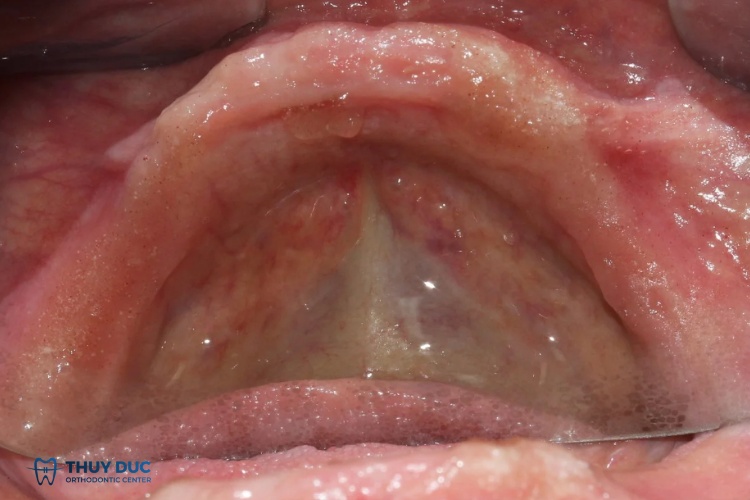

Hình ảnh khách hàng sử dụng hàm giả tháo lắp tại Nha khoa Thúy Đức